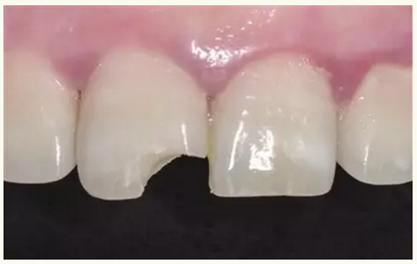

牙體樹脂美學(xué)修復(fù)適用于對(duì)牙體修復(fù)效果有美學(xué)要求的前牙或者后牙。對(duì)于患者而言,前牙修復(fù)效果更為直觀。因此,臨床上對(duì)于前牙美學(xué)修復(fù)的需求更為迫切,常見的修復(fù)類型為及切角的前牙牙體缺損。治療的過程一般為①比色、②缺損牙體的樹脂預(yù)修復(fù)(直接修復(fù))或者取模翻制石膏模型的基礎(chǔ)上制作蠟型恢復(fù)缺損牙體(間接修復(fù)),③硅橡膠制作舌側(cè)導(dǎo)板,④上橡皮障,牙體預(yù)備(洞緣斜面),⑤酸蝕、粘結(jié),⑥樹脂分層充填,⑦修形、拋光,⑧完成。

▲術(shù)前(唇側(cè))

▲術(shù)前(舌側(cè))